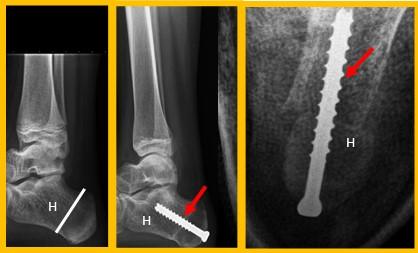

Extenderende Osteotomie 1e straal

Hierbij wordt de grote teen omhoog geplaatst door een botwigje uit te zagen aan de basis van de grote teen. Door dit wigje te verwijderen kan de grote teen omhoog komen waardoor de holling in de voet minder wordt. De voet wordt dus platter en beter belastbaar. Op de plaats waar we het botwigje hebben verwijderd plaatsen we een RVS schroefje en ijzerdraadje om het middenvoetsbeentje van de grote teen op de juiste positie te houden. Zodra het bot genezen is, is de schroef niet meer nodig en kan bij klachten evt worden verwijderd.

Figuur 4: Het bovenste linker plaatje is een schematische weergave van de “osteotomie”. Het driehoekje bij de pijl wijst naar de wig die uitgezaagd wordt. Het plaatje eronder laat de situatie zien na verwijderen van het wigje. Het middelste plaatje laat een voetfoto van een patiënt zien voor de operatie, de witte streep is de plaats van het litteken. het meest rechtse plaatje is na de operatie. Bij de pijl zie je de schroef en het ijzerdraadje om de botdelen op de juiste positie te houden.